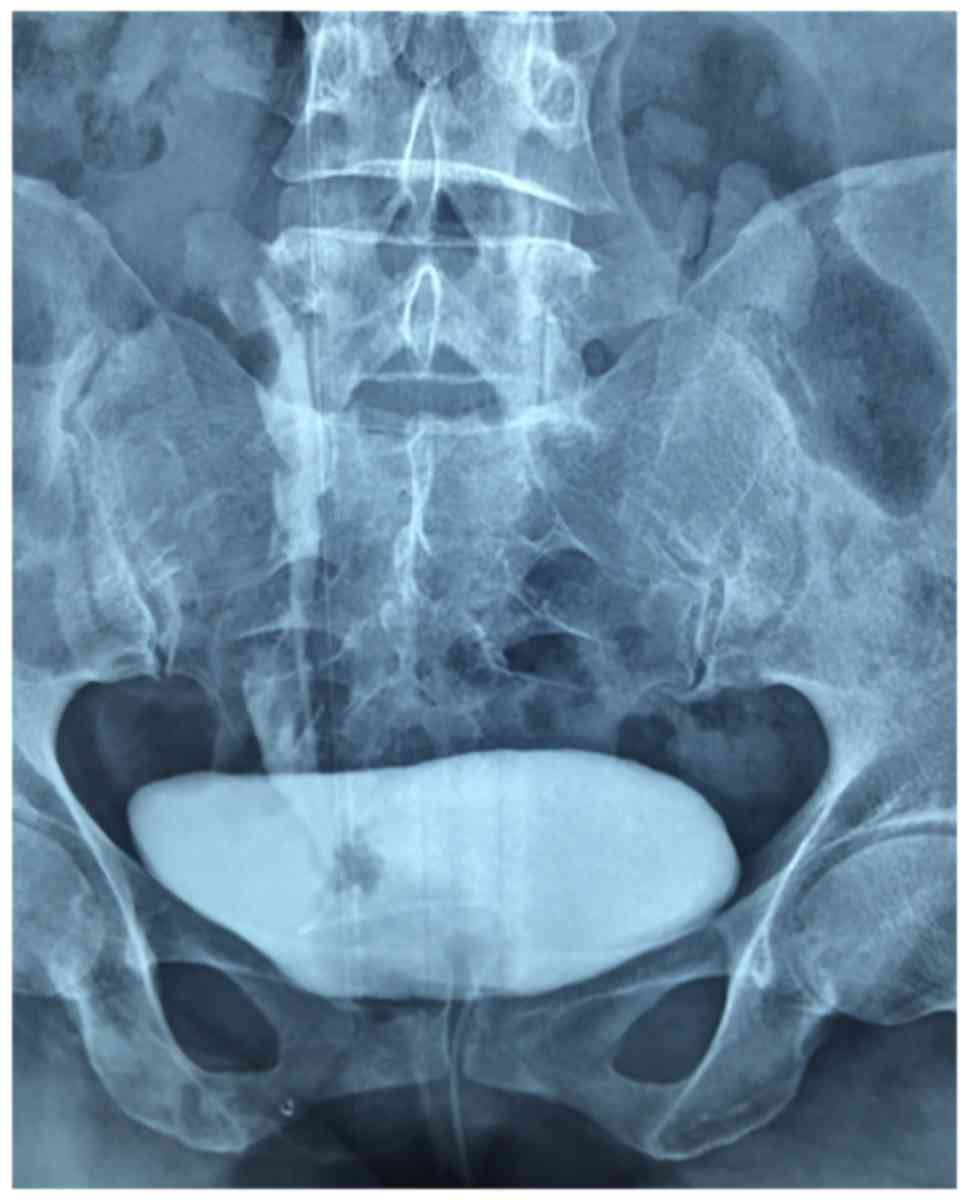

A 53-year-old woman was admitted to the Second Clinical Hospital of North Sichuan Medical College (Nanchong, China) with gross painless hematuria for ~2 years and frequency of urination for ~1 month. The physical examination was unremarkable. Multidetector computed tomography urography (CTU) revealed a filling defect in the lower part of the right ureter (Fig. 1). Cystoscopy revealed a mass ~3 cm in length, with a smooth surface, protruding from the ureteral orifice into the bladder (Fig. 2). Examination of a bioptic specimen suggested that the mass was an inflammatory polyp. A 5F ureteral catheter was inserted from the right ureteral orifice; ~10 cm after the insertion point, resistance was encountered and the catheter could not be advanced further. Retrograde urography was subsequently performed and the contrast media failed to reach the upper part of the ureter and the renal pelvis, whereas the lower part of the ureter exhibited a filling defect (Fig. 3).

Figure 3.

Retrograde urography showing a filling defect in the right lower ureter and no contrast medium in the upper ureter and renal pelvis.